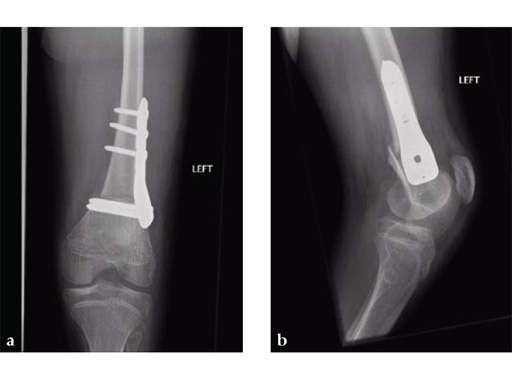

Osteotomies were stabilized with the 5.0 mm LCP pediatric condylar plate. Postoperative management was non-weight bearing in splints, followed by weight bearing and rehabilitation at 6 weeks. Osteotomies healed uneventfully.

Case provided by James B Hunter, Nottingham, UK